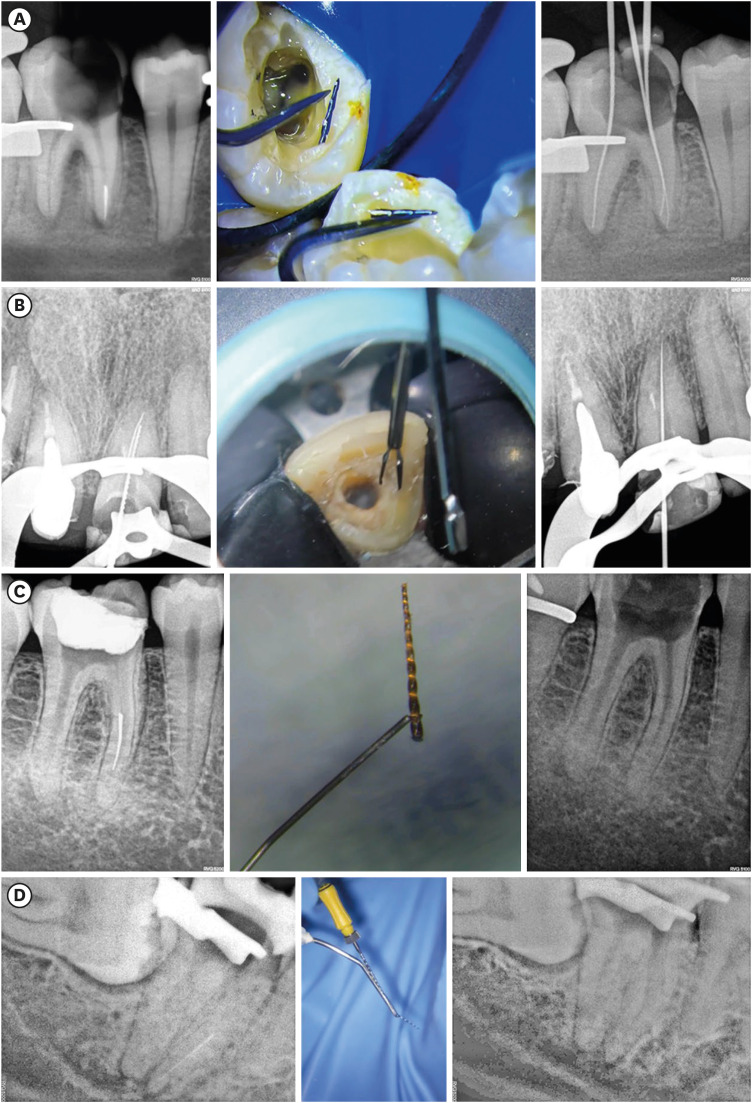

Computer-Guided Bone Lid Technique for Surgical Extraction。Advanced Material Strategy for Restoring Damaged。Predictive factors in the retrieval of endodontic。⚜️Ninja endodontic cavities and conservative endodontic。裁断済みのため状態は悪いにしています「How to Endodontics The State of the Art : ビジュアライズドイラストレーションズ」寺内 吉継定価: ¥ 13600#寺内吉継 #寺内_吉継 #本 #自然/医療・薬学・健康。